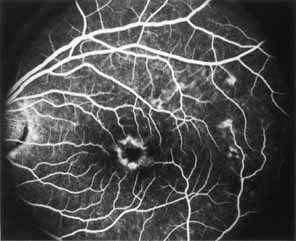

During the early stage of the dystrophy, when patients demonstrate a slight-to-moderate decrease in visual acuity and minimal color defects, there are minor or no visible fundus abnormalities. At most, the foveal reflex may be absent and there may be some increased granularity of the retinal pigment epithelium in the macula. Later, there is a decrease of visual acuity to the 20/400 range, oval atrophy of the macular retinal pigment epithelium (“beaten bronze” atrophy), and associated choroidal atrophy (Fig. 3). A characteristic bull's-eye maculopathy, similar to that seen in patients with chloroquine retinopathy, may also be seen.90 Photophobia, occasional nyctalopia, incomplete-to-complete color defects, and a central scotoma are often present. The symmetry of the process in both eyes is remarkable.

Fluorescein angiography demonstrates increased transmission of choroidal fluorescence in the macula during early phases of the study, without late leakage of dye or fluorescein staining. In addition, an annular pattern of hyperfluorescence is often seen in the macula, highlighting the bull's-eye pattern seen on fundus examination (Fig. 4). Visual field defects include central scotoma, peripheral field loss, and ring scotoma.